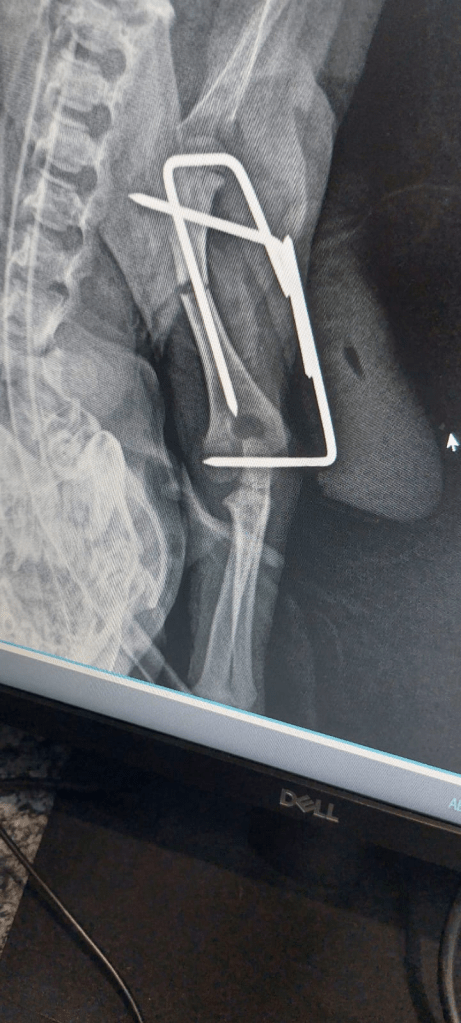

Norm took her to the vet the next morning for her surgery and we picked her up at 4pm. The receptionist said that she yelped so much when in the cage on her own they had to hold her to shut her up. She was wide awake when she and Norm came home. He showed me a copy of an Xray from the vets. It looks like they used a large paper clip.